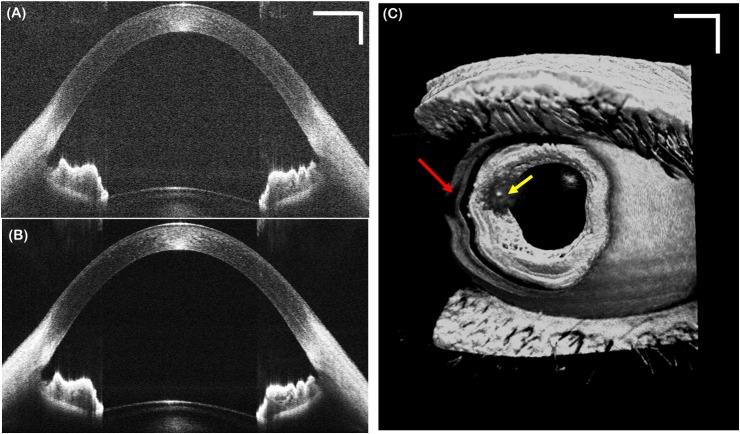

Volumetric acquisition with anterior segment optical coherence tomography (ASOCT) is necessary to obtain accurate representations of the tissue structure and to account for asymmetries of the anterior eye anatomy. Additionally, recent interest in imaging of anterior segment vasculature and aqueous humor flow resulted in application of OCT angiography techniques to generate en face and 3D micro-vasculature maps of the anterior segment. Unfortunately, ASOCT structural and vasculature imaging systems do not capture volumes instantaneously and are subject to motion artifacts due to involuntary eye motion that may hinder their accuracy and repeatability. Several groups have demonstrated real-time tracking for motion-compensated in vivo OCT retinal imaging, but these techniques are not applicable in the anterior segment. In this work, we demonstrate a simple and low-cost pupil tracking system integrated into a custom swept-source OCT system for real-time motion-compensated anterior segment volumetric imaging. Pupil oculography hardware coaxial with the swept-source OCT system enabled fast detection and tracking of the pupil centroid. The pupil tracking ASOCT system with a field of view of 15 x 15 mm achieved diffraction-limited imaging over a lateral tracking range of +/- 2.5 mm and was able to correct eye motion at up to 22 Hz. Pupil tracking ASOCT offers a novel real-time motion compensation approach that may facilitate accurate and reproducible anterior segment imaging.